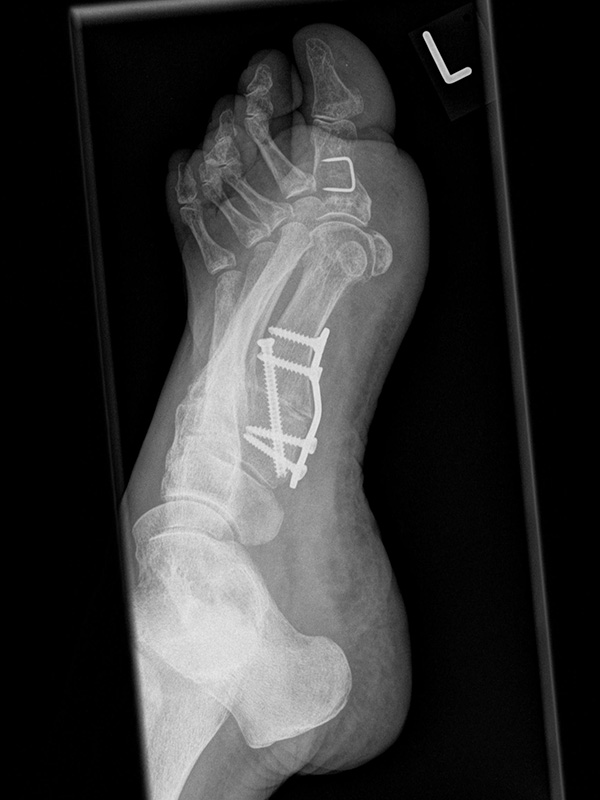

• Die 45° Supinationsaufnahme wird häufig eingesetzt, um die knöcherne Konsolidierung einer Lapidus-Arthrodese zu beurteilen.

• Hier das Beispiel 6 Wochen postoperativ nach Tarsometatarsale I Fusion mit Stabilisierung durch eine plantare Platte.

• Die Arthrodese zeigt sich weitgehend überbaut bei korrekter Lage des Osteosynthesematerials.